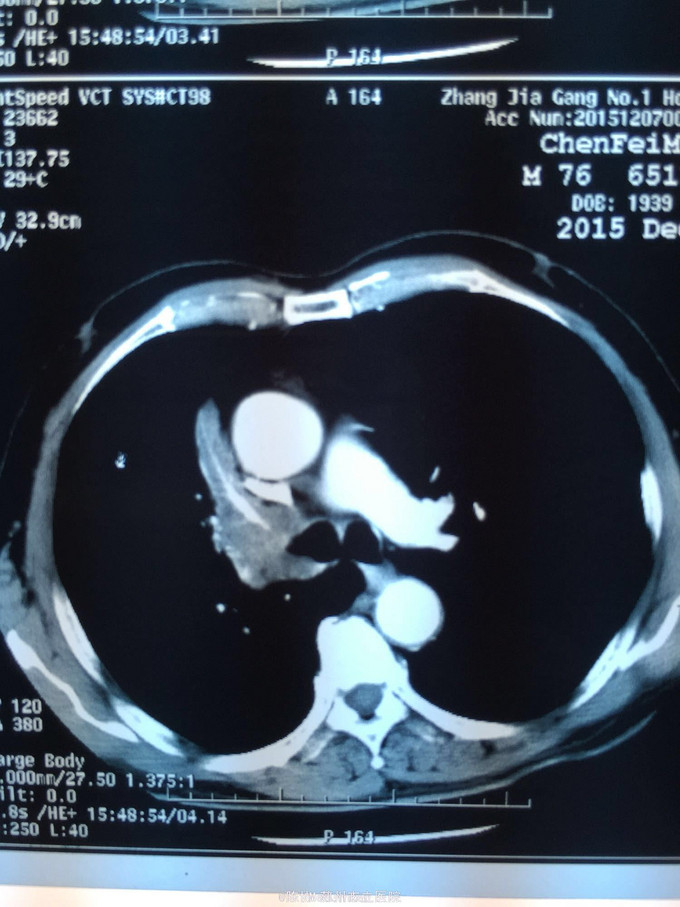

主诉:体检发现右上肺不张半月 77岁男,半月前体检发现右上肺不张,无不适。无消瘦,无咳血,无干咳。去年4月右上肺炎,抗生素治愈,当时CT未见肺肿块。入院支气管镜发现右上支气管开口组织增厚闭塞,开口近侧有隆起约3x3平方毫米,取活检5块病理示中度非典型增生。CT提示在右侧主支气管外侧有30x30平方毫米块影,压迫右上支气管开口处。三大常规和生化检查正常,肿瘤指标正常,TAP正常。

右侧中央型肺癌 重做支气管镜,精于定位找到病症组织,获得病理诊断来指导治疗。 胸外科医生不建议手术,理由是肿瘤位置靠近主支气管和气管,袖状切除不一定看干净。 请问正确的诊断,和比较合理的治疗方法是什么?求助大家思考评论